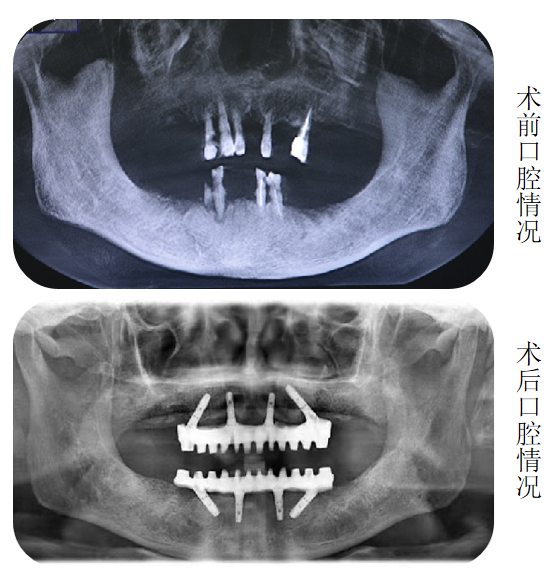

“这个您不用担心。”海涛口腔种植科唐主任经过口内数据分析和会诊后告诉李大妈:“我们借助计算机,设计出您口腔内8个适合种植的位置,利用海涛“一天得”全口种植牙技术,上下半口各4颗种植体就能分别完成半口牙修复,恢复全口咀嚼功能。”

上午进入手术室时还是无牙状态的李大妈,下午出来时已戴上固定义齿,激动地说:“海涛口腔的技术真是了不起,我这多年的缺牙问题终于解决了。”

海涛口腔唐主任介绍,海涛“一天得”全口种植牙是海涛口腔的特色技术,数字化导航定位,植入精准,只需植入4颗或6颗种植体就可以解决半口无牙问题,并且当天种牙,当天就可戴牙吃饭。整个手术过程一次性完成,大大缩短了患者的就诊时间和次数,节省了治疗费用,价格相比传统种植牙省了很多。同时,该技术采用2毫米的钛丝,结合国际先进的口内冷焊接技术焊接而成,稳定性非常好。与此同时,该技术打破传统种植技术瓶颈,破解牙槽骨萎缩、骨量不足等种植难题,无需植骨不增加额外费用,让这一缺牙群体也能实现种植牙。